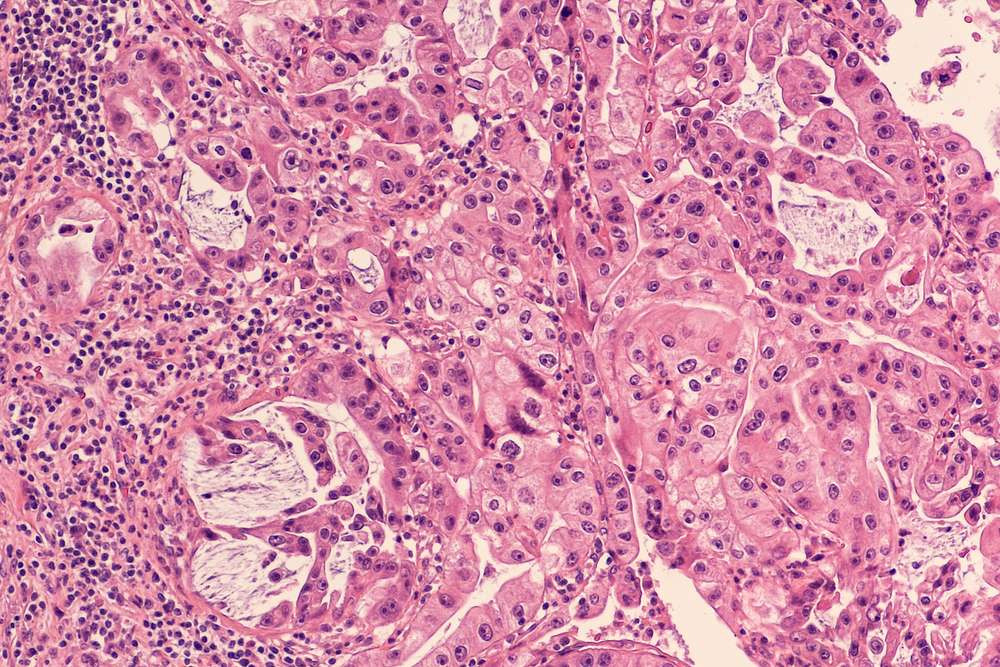

Biopsia de pancreas reprezintă o metodă exploratorie cu rol diagnostic ce presupune prelevarea unei probe de țesut de la nivel pancreatic, cu scopul identificării naturii unor leziuni, precum și a gradului lor de evoluție și severitate. Această biopsie se poate realiza atât percutanat, prin ghidaj imagistic, cât și prin intermediul laparotomiei exploratorii. Proba este trimisă către laborator, cu scopul efectuării unui examen histopatologic.

Indiferent de metoda pentru care se optează, proba de țesut pancreatic este trimisă către laborator, unde este prelucrată și pregătită pentru examenul histopatologic. În cadrul examenului histopatologic, se pot evidenția prezența celulelor tumorale, tipul celular al acestora, precum și stadiul evolutiv al neoplasmului.